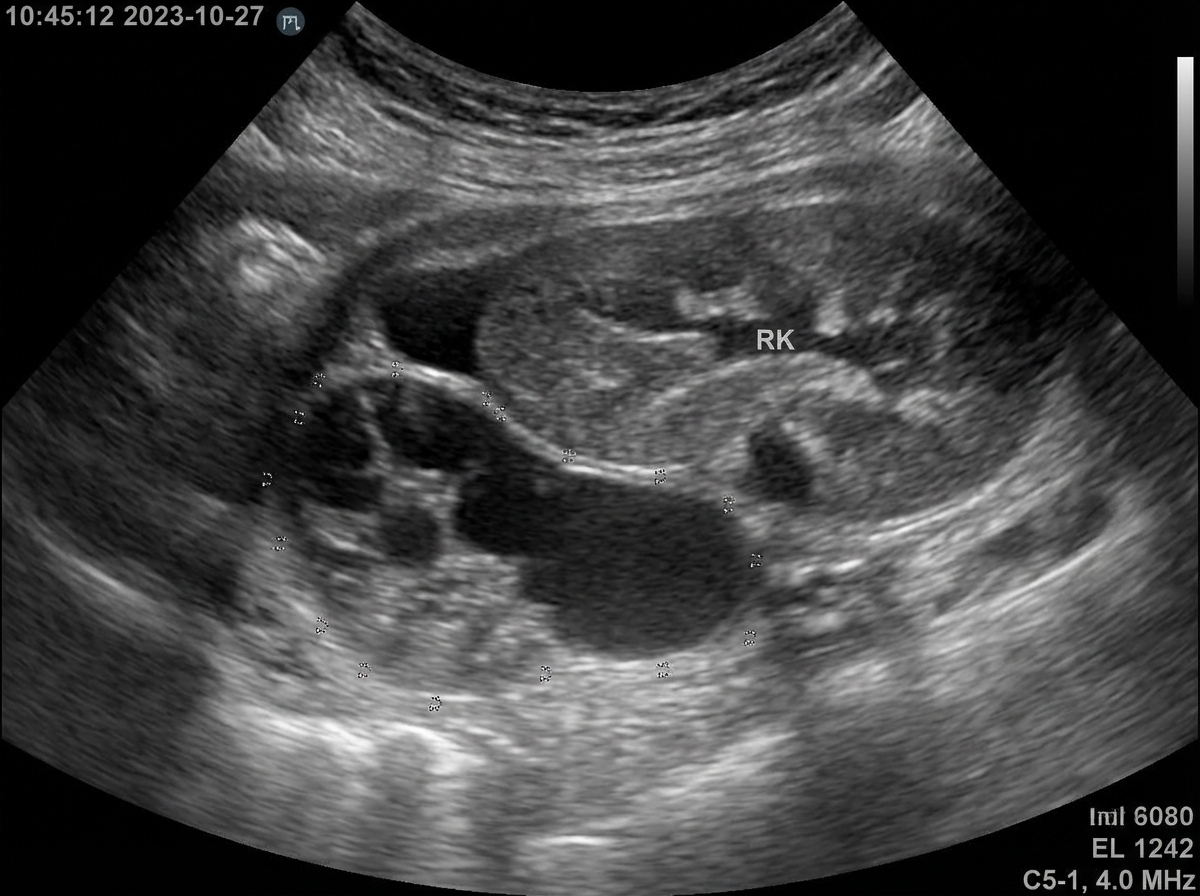

A 57-year-old male is admitted to the hospital for a suspected kidney infection (likely pyelonephritis). The patient is placed on intravenous antibiotic therapy but continues to have a temperature of 103°F after 3 days of therapy. The urine culture grows lactose-fermenting Gram-negative bacilli which are pan drug-sensitive. On examination, he appears ill and has marked left flank tenderness. Ultrasound depicts a specific finding. What is the most likely diagnosis?

Explanation: ***Perinephric abscess*** - **Persistent high fever** despite 3 days of appropriate antibiotic therapy in pyelonephritis strongly suggests **abscess formation**, as antibiotics cannot penetrate well into enclosed collections. - Ultrasound would show a **hypoechoic fluid collection** in the **perinephric space** surrounding the kidney, which is the key diagnostic finding. *Hydronephrosis* - Would present with **obstructive symptoms** and **dilated renal pelvis** on ultrasound, not persistent fever after antibiotic treatment. - Usually associated with **decreased urine output** and **relief of pain** with positioning, unlike this case. *Nephrolithiasis* - Typically presents with **colicky pain** that radiates to the groin, not constant flank tenderness. - Ultrasound would show **echogenic stones** with **acoustic shadowing**, and fever would resolve with antibiotics if infection was present. *Emphysematous pyelonephritis* - Occurs primarily in **diabetic patients** and involves **gas-forming bacteria** creating emphysema in renal parenchyma. - Ultrasound would show **hyperechoic foci** with **dirty shadowing** from gas, and the organism is typically **Klebsiella** or **E. coli**, not just any lactose-fermenter.